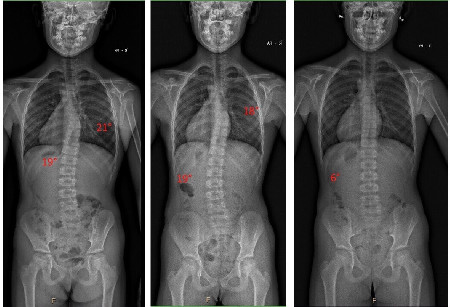

U starších dětí s úspěchem řešíme časté problémy s vadným držením těla nebo plochou nohou. Specializujeme se na terapii idiopatické skoliózy. Dlouhodobou prací opravujeme držení těla tak, aby se nemuselo vychýlení páteře řešit operací.

V našem týmu naleznete odborníky specializující se na psychomotorický vývoj novorozenců či kojenců. Společnou prací dosáhneme zlepšení stavu i v případě vážnějšího problému např. dětské mozkové obrny nebo adolescentní skoliózy.